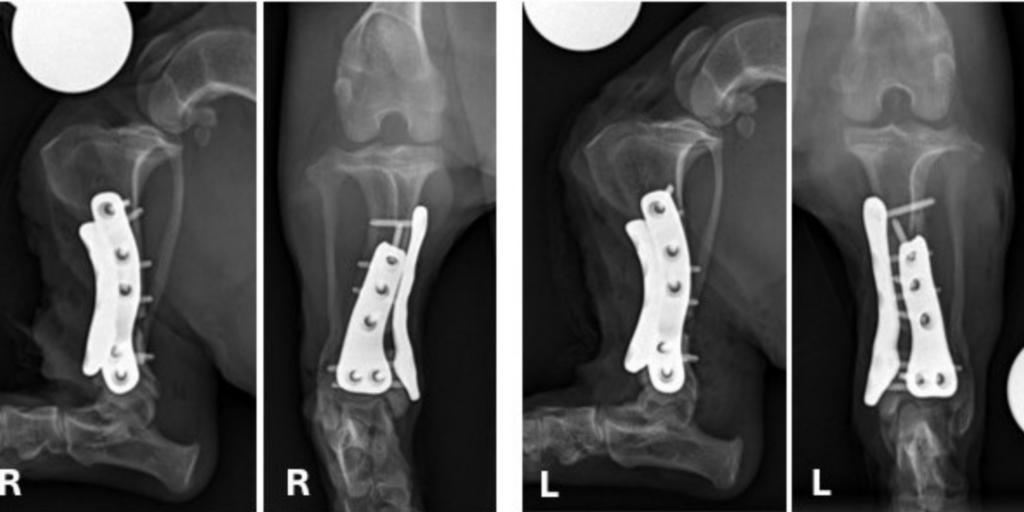

They agreed Chunk needed surgery to correct the deformity, so Bleedorn worked with Dr. Bill Oxley of Vet3D, a 3D consulting company in the United Kingdom, to create custom 3D-printed surgical guides and titanium plates.

“You can import the CT into the computer-aided design (CAD) software, so you can look at the bones and their alignment on the computer,” Bleedorn said. “Then we can actually do a virtual correction rehearsal surgery all on the computer where I cut the bones and manipulate them, so I know precisely what my target plan will be. Once I’m happy with the plan, then I will build a guide that ensures I can make the cuts in the right spot in surgery.”

It sounds futuristic, but the technology has been in use for about 20 years in veterinary medicine. “The guide is printed, sterilized, and then physically placed on the tibia and secured with pins onto the bone and we basically cut on the guides like a 3D template,” Bleedorn said. “Custom metal printed plates are a more recent addition to this approach but allow tremendous opportunity for improvements in challenging cases such as Chunk.”

In May, Bleedorn, CSU orthopedic surgeon Dr. Joey Sapora, and resident Dr. Zach Wund performed the procedure. They cut and fixed the bones with custom 3D-printed guides and two tiny titanium plates in each leg. “The repair is very strong because the plates fit perfectly on Chunk’s tibiae,” Bleedorn said.